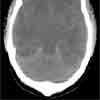

The approach to managing DKA is unique in children because of the potential for the most dreaded complication--acute cerebral edema, which affects only youngsters10 and complicates 1 in 100 episodes of pediatric DKA (Figure).10,11 Acute cerebral edema is lethal in 20% to 50% of children (this rate has remained constant for years).4 A third of affected children suffer serious neurologic sequelae and disability.10

Some patients have subclinical brain edema even before treatment is initiated. Therefore, treatment may exacerbate but does not cause cerebral edema. Watch for signs and symptoms of increased intracranial pressure (eg, headache, hard to arouse, vomiting, change in mentation). Affected children need emergent CT scans of the head as well as neurosurgical consultation. Care must be taken not to hyperventilate an intubated patient. Hyperventilation decreases cerebral blood flow, which exacerbates ischemia.